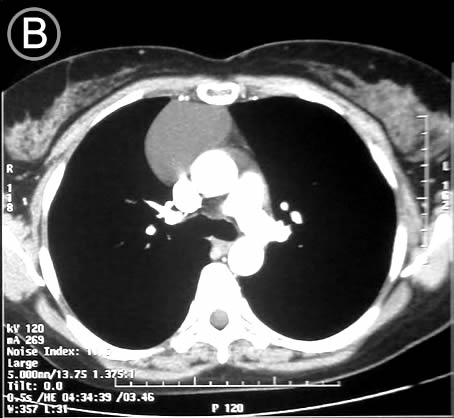

Corte Tomográfico B

Sección transversal mas bajo, a la altura de la carina traqueal:

Lesión por delante del cono aortico y de la vena cava superior, mantiene las características descritas.